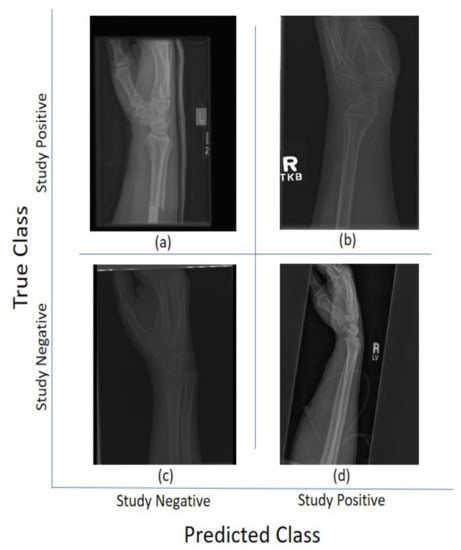

For the 11 architectures with no data augmentation, Inception-Resnet-v2 performs the best with an accuracy ( A c = 0.723 ) and Cohen’s kappa ( κ = 0.506 ). DenseNet-201 fares slightly lower ( A c = 0.717 , κ = 0.497 ). The lowest results were obtained with GoogleNet ( A c = 0.654 , κ = 0.381 ). This potentially indicates better feature extraction with deeper network architectures. Figure 5 and Figure 6 illustrate some cases of the classification for Lateral and Postero-anterior views of wrist radiographs.

Figure 5. Illustration of classification results for lateral (LA) views of wrist radiographs. (a) Corresponds to positive (abnormal) diagnosis image but predicted as negative (normal), (b) Abnormal diagnosis and abnormal prediction. (c) Normal diagnosis image and normal prediction. (d) Normal diagnosis and abnormal prediction. Notice that the errors in classification may have been biased by artefact elements on the images.

Figure 6. Illustration of classification results for postero-anterior (PA) views of wrist radiographs. (a) corresponds to a positive (abnormal) diagnosis image that is predicted as negative (normal); (b) to abnormal diagnosis and abnormal prediction; (c) to normal diagnosis image and normal prediction; and (d) to normal diagnosis and abnormal prediction. Notice again that the errors in classification may have been biased by artefactual elements on the images.